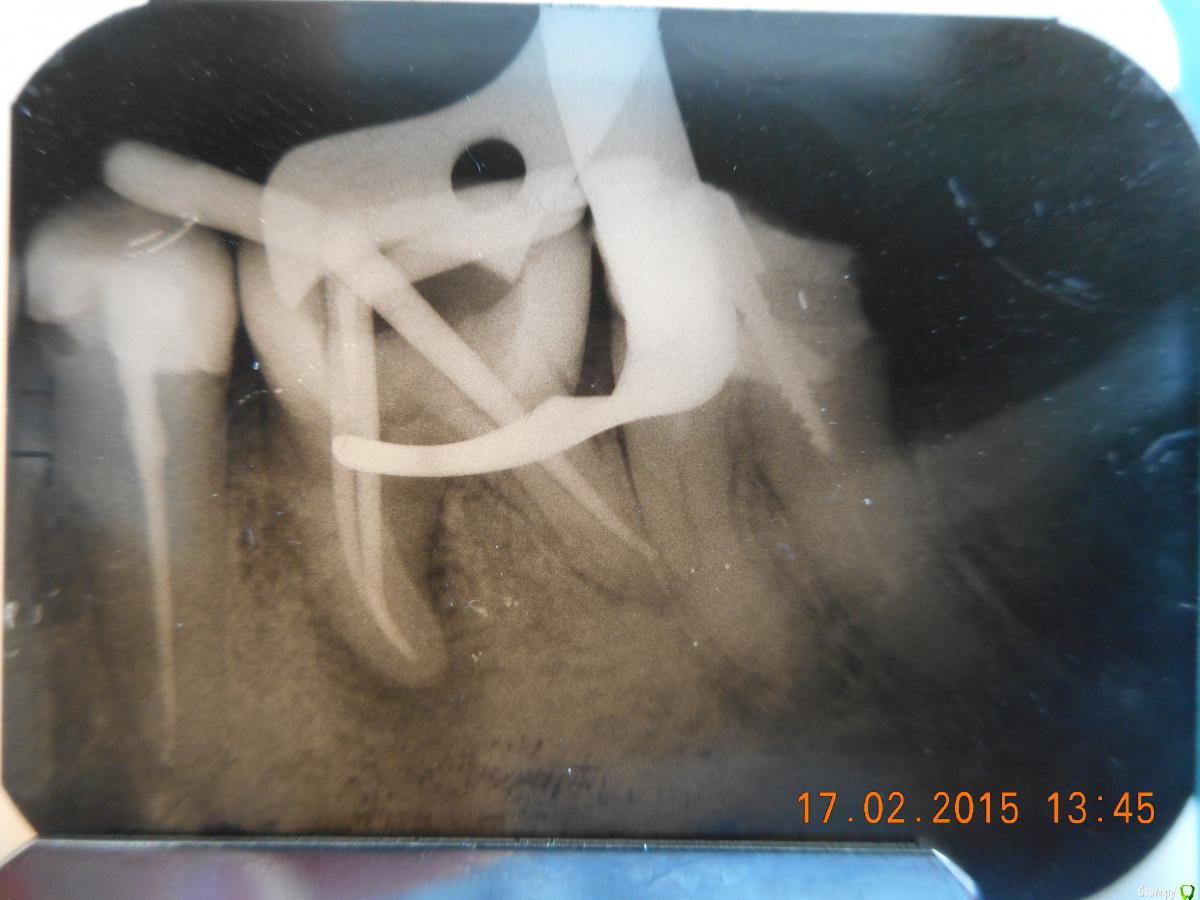

Dr.Feliks Опубликовано 17 февраля, 2015 Автор Поделиться Опубликовано 17 февраля, 2015 Как и обещал - снимок на этапе лечения зуба (до лечения только КТ - т.к. лечение было плановое). Ссылка на комментарий